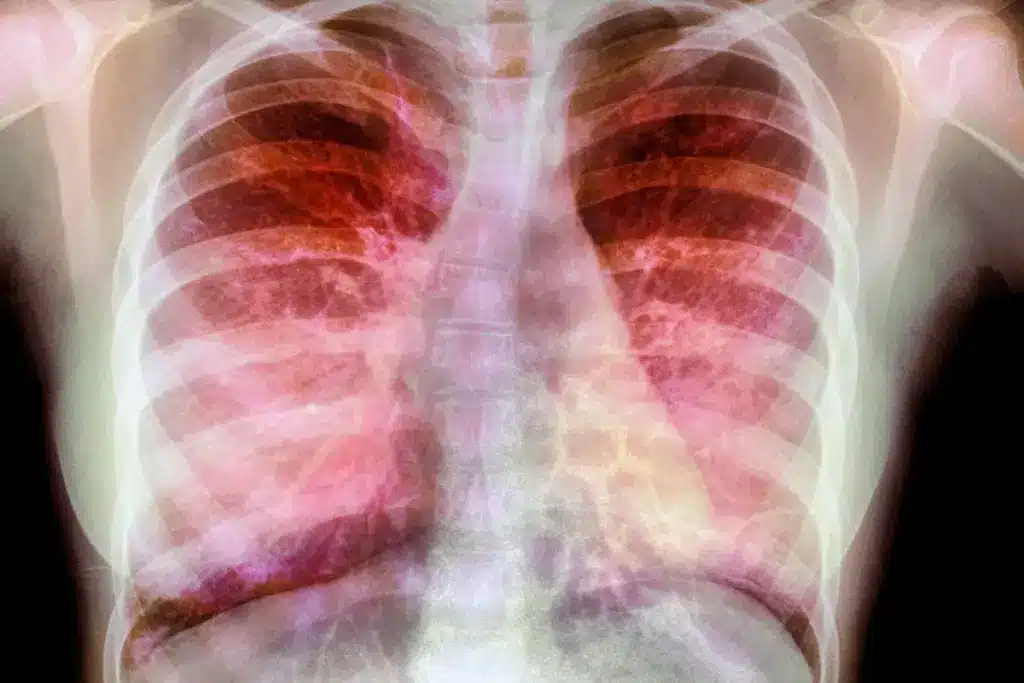

Phlegm is more than just a nuisance; it’s a protective shield for our lungs. It traps dust, bacteria, and other harmful particles, keeping them from reaching our lungs. Understanding its role and color can give us insights into our health.

Phlegm catches harmful particles we breathe in, like dust and viruses. It keeps our lungs clean and protects us from infection. The mucociliary clearance mechanism moves phlegm up towards our throat, where it can be swallowed or coughed out.

Knowing how phlegm protects us helps us understand why its color or amount can change. For example, more phlegm or a different color might mean we have an infection or respiratory problem.